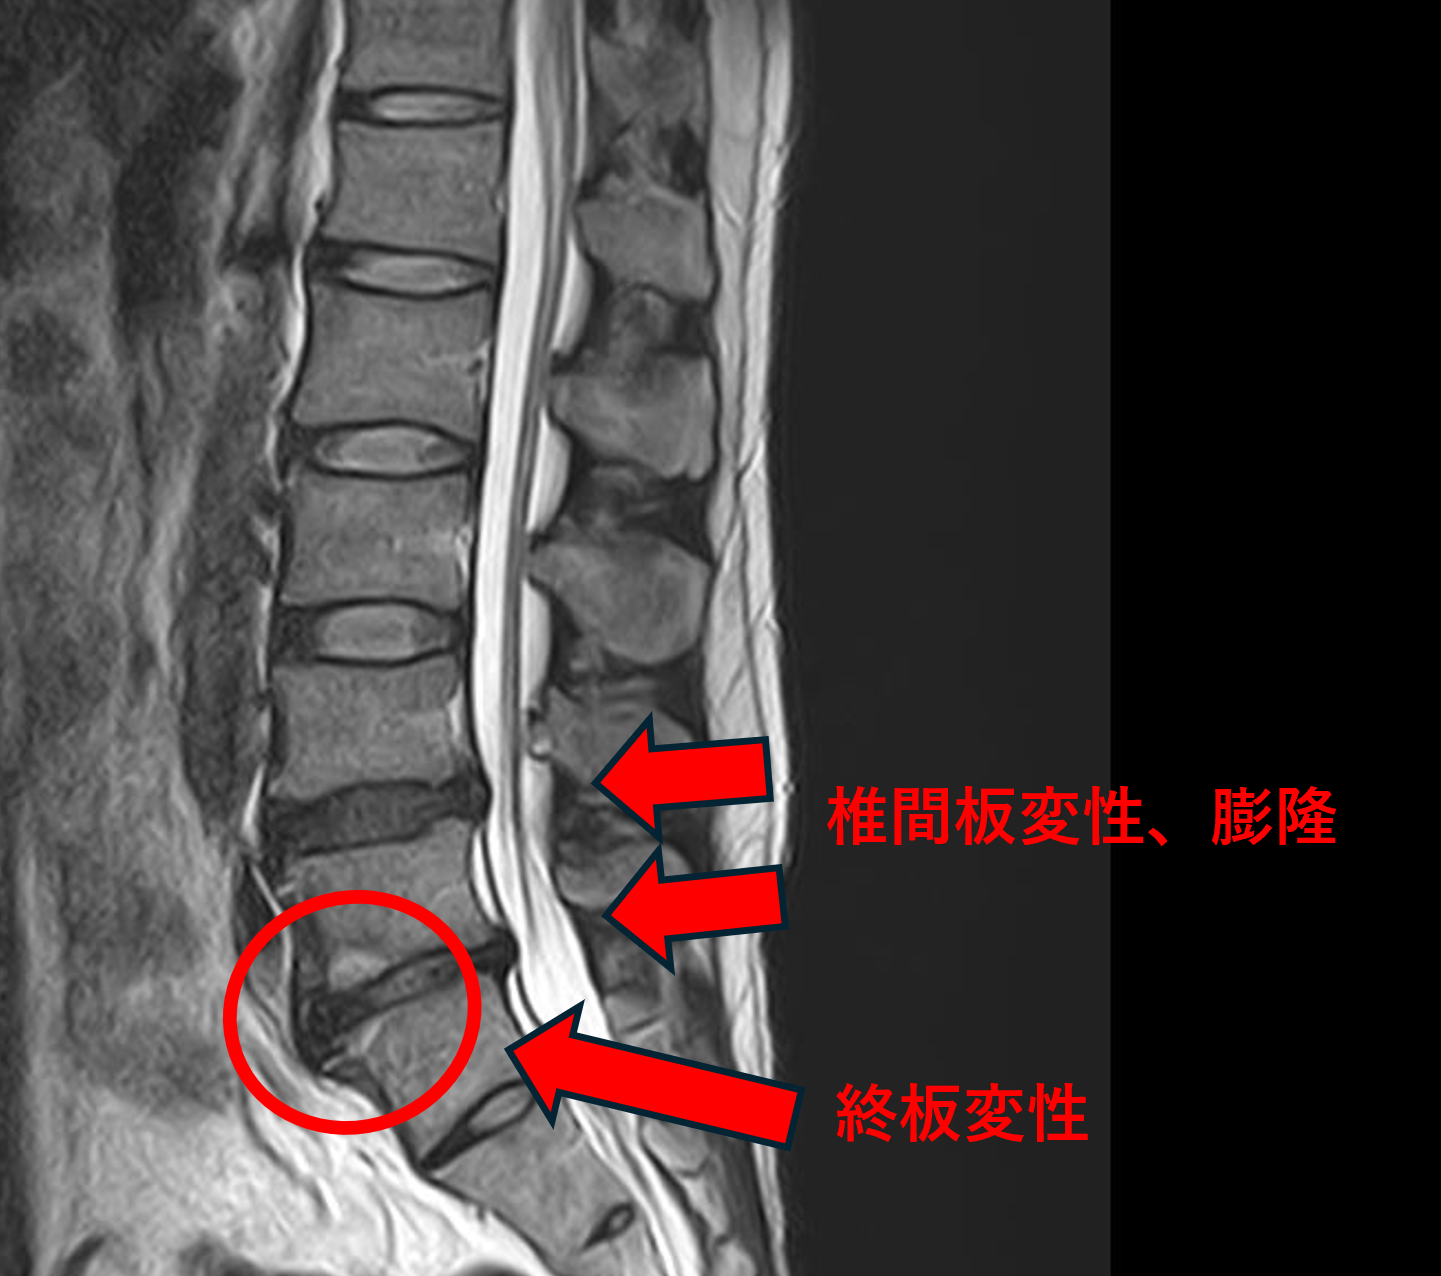

画像及び所見について

- L4/5 – 椎間板変性、膨隆

- L5/s – 椎間板変性、膨隆、終板変性

以上のことが画像上認められました。

L4/5、5/sの椎間板所見による脊柱管の圧排が、症状の原因の可能性がもっとも高い。